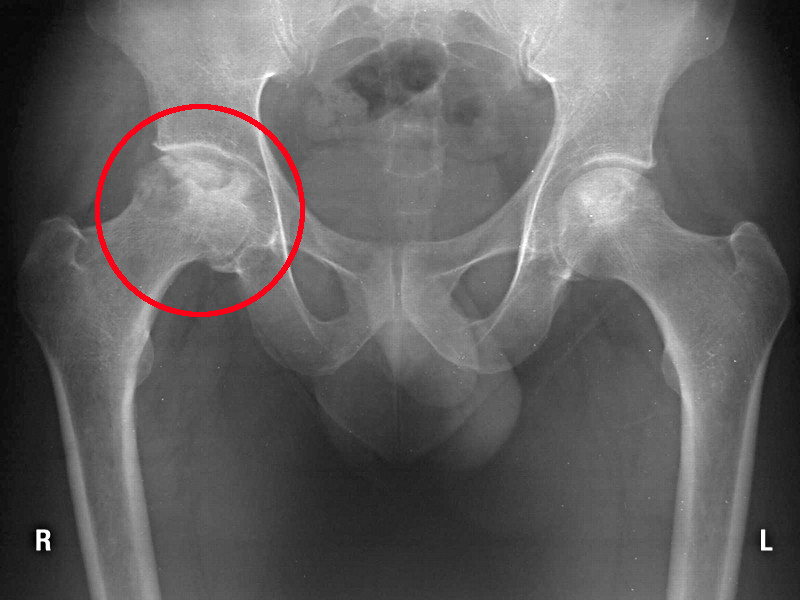

La protesi d'anca viene impiantata quando sia presente una importante sintomatologia dolorosa all'articolazione coxo-femorale, in presenza di immagini radiologiche che mostrino la presenza di:

- artrite/artrosi: condizione per la quale uno stato infiammatorio acuto o cronico determina una alterazione delle cartilagini articolari ed una riduzione dello spazio articolare, con formazione di osteofiti.